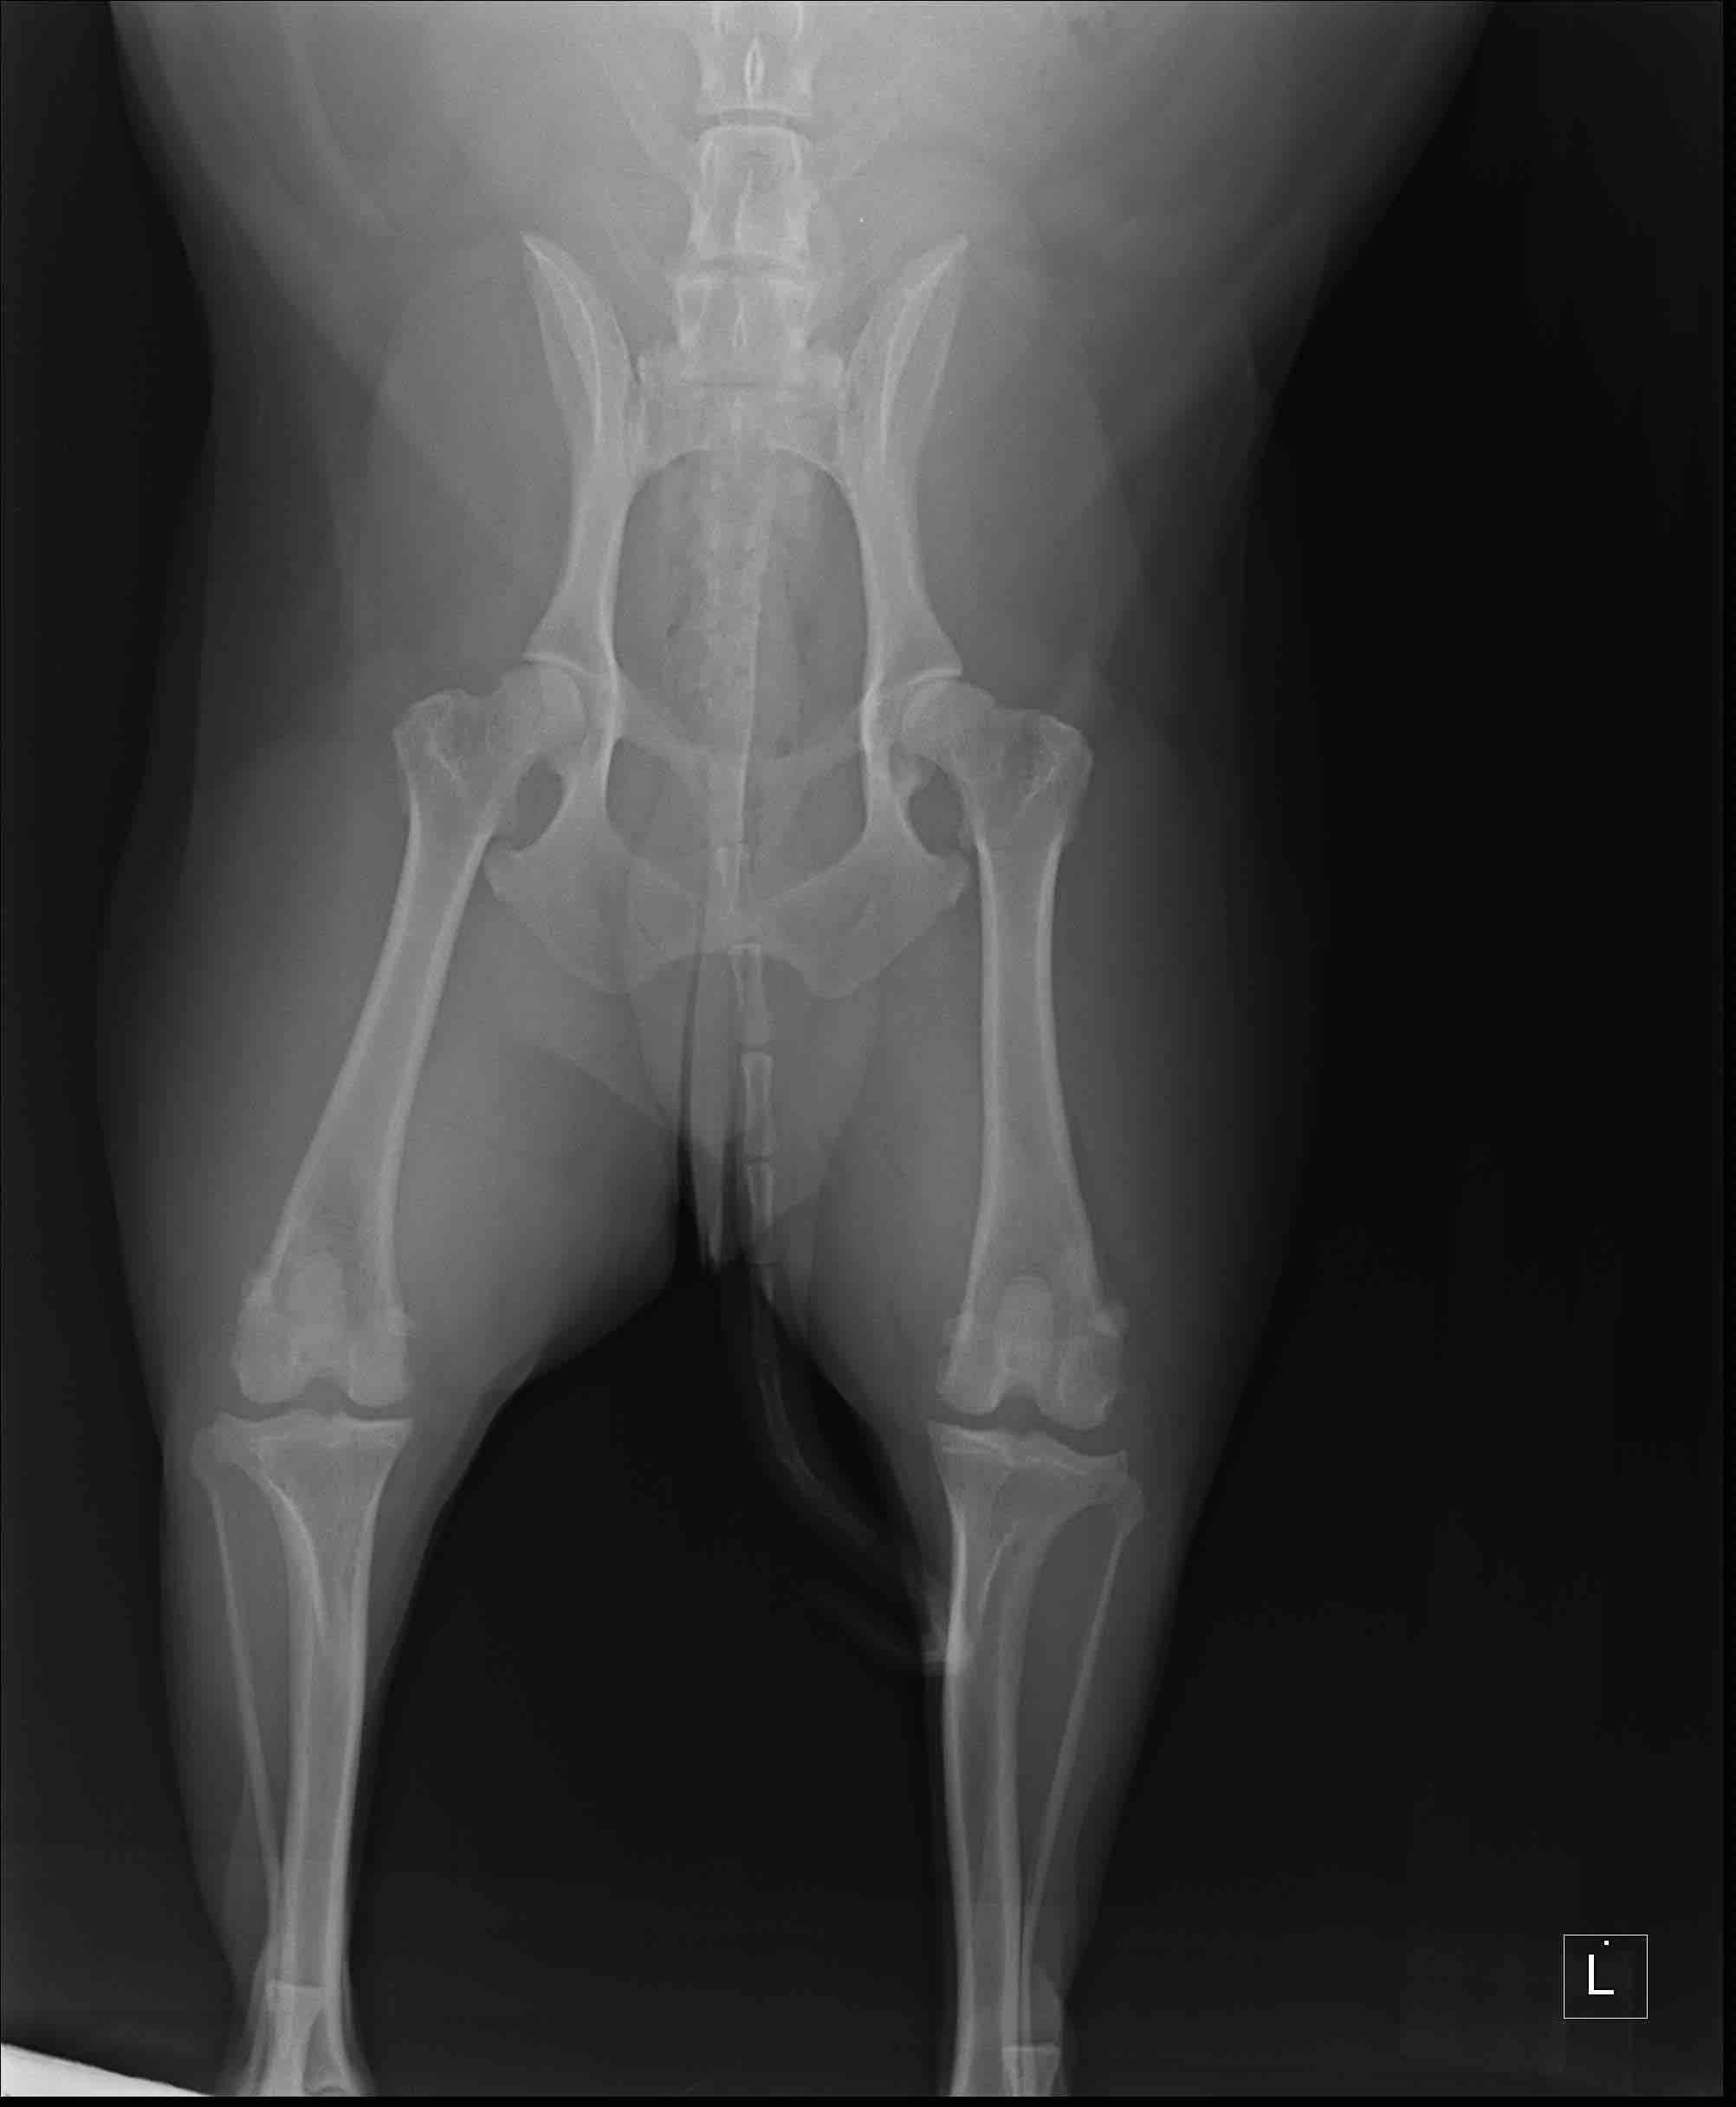

Brody has been having lameness in his hind legs. He was put on meds for inflammation and it still continued. Went back for X-ray. Vets seem to think arthritis. We then started him on dasuquin three weeks ago. He is still experiencing lameness in his hind legs. Should he be showing improvement by now if it is arthritis? Also xrays did show bladder stones which i understand can cause pain in abdomen. Could it present as leg pain to us? I’m attaching his X-rays. Should i seek second opinion? Thanks

I hate to hear that Brody is experiencing some issues with his legs. I agree that the hips look like they could be the source of the lameness with decreased acetabular coverage of the femoral heads and also a slight thickening of the femoral necks. I do not anticipate lameness from the bladder stones. Discomfort from the bladder stones tends to occur when Brody urinates and I have seen some pets exhibit no signs. You may discuss with the veterinarian ways to address the stones as they can cause problems with urinary tract infections or even cause obstruction of the urethra. Most pets will have surgery although depending on the type of stone, some may be able to break down with a special diet. Regarding the lameness, Dasuquin is a good product and it will take 4-6 weeks to reach maximum strength. Most vets recommend loading the supplement (so they take a higher amount for 4-6 weeks) then they decrease it. Give it a little more time to take effect. Other things that can help with arthritis including giving an additional omega 3 fatty acid (Nutramax makes a nice product) can help with natural inflammation control. There is another product I like called Duralactin and it is a joint supplement that I often use in conjunction with Dasuquin. If you are interested in a diet change, Royal Canin makes a diet called Mobility Support which has green lipped muscle as an ingredient and pets tend to do very well in it. Lastly, you make consider seeking a veterinarian or facility who can offer physical therapy. Especially with the hind legs, muscle mass and tone is very important in stabilizing the joints. Daily, low impact activity is very important in maintaining this. A physical therapist will examine the lameness and all the muscle groups and will show you exact exercises you can do at home to maintain optimal muscle health. Long term, this is very important. Sometimes the therapist will recommend other things like working on an under water treadmill, swimming or even acupuncture to help. It’s definitely beneficial to get therapies started early while the signs are still mild. Certainly if Brody does not respond well after 6 weeks, I think seeking a second opinion is valid. I hope this helps and thank you for using Petco Pet Education Center, formerly Petcoach.